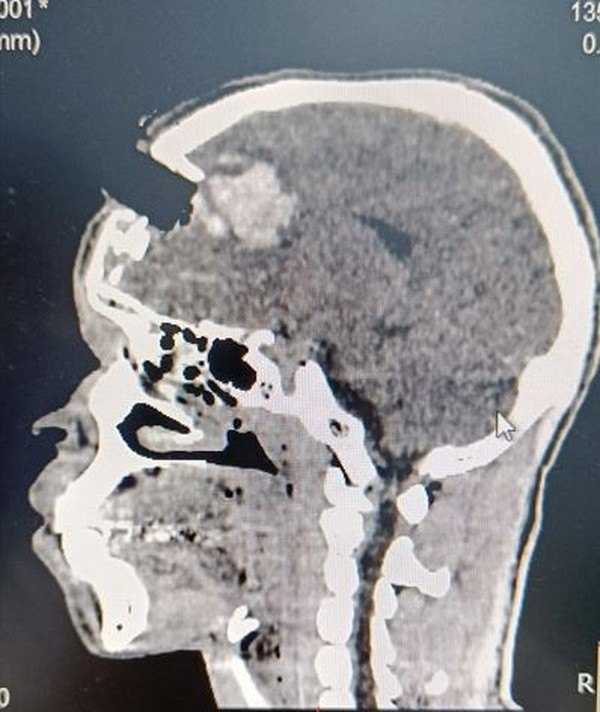

Segundo atualização doa médicos responsáveis, dada na quinta-feira (11), o quadro dele é "potencialmente grave, porém estável". Vitor teve o lóbulo frontal direito atingido e, apesar da gravidade, está lúcido, falando e sem danos aparentes na memória ou mobilidade dos quatro membros.